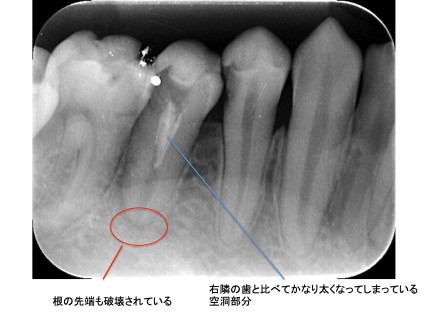

こちらは虫歯で神経を取らないといけなくなりましたが、何度治療しても痛みが消えないと言うことで当院にいらっしゃいました。度重なる治療で歯の神経のあった場所がかなりひろげられており、また根の先端も破壊されている状態でした。ですので、痛みが消えないのです。

肉眼では根の先端は見ることができませんがマイクロスコープでは見ることができます。根の先端をこれ以上破壊しないように清掃して歯の神経があった場所にお薬を詰めることができました。根の治療後、かぶせ物までして半年たっても痛みがありません。

レントゲンを見ていただいて、歯の先までしっかり白いお薬が入っているのがわかります。